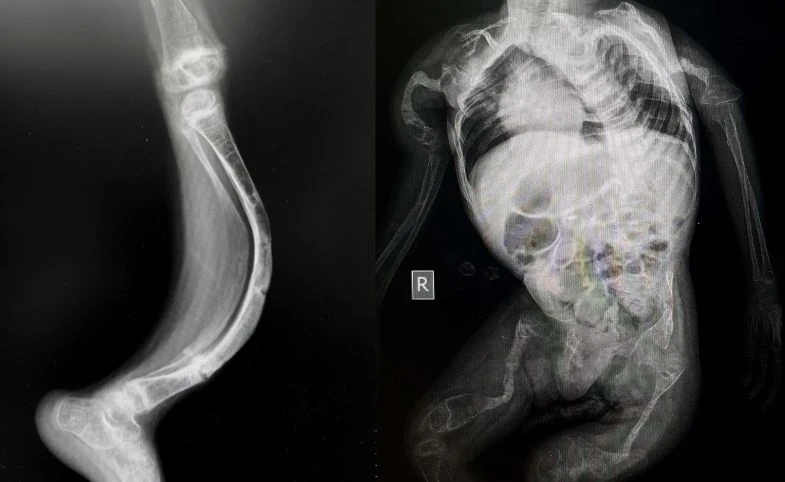

Salah satu bagian paling menyentuh dari kisah Zehan Almira adalah kondisi kesehatannya. Zehan didiagnosis mengidap Osteogenesis Imperfecta (OI), penyakit genetik langka yang menyebabkan tulang menjadi rapuh dan mudah patah karena kekurangan kolagen tipe I. Kondisi ini terdeteksi sejak dalam kandungan, di mana beberapa tulang Zehan sudah mengalami patah. OI bukan penyakit yang bisa disembuhkan total, tapi bisa dikelola dengan terapi dan perawatan rutin untuk memperkuat tulang.

Gejala OI pada Zehan membuat pertumbuhannya lebih lambat, postur tubuh mungil, dan dia harus ekstra hati-hati dalam beraktivitas. Itulah alasan Zehan masih sering digendong meski usianya sudah 7 tahun, untuk menghindari risiko cedera. Untungnya, OI tidak memengaruhi perkembangan intelektual Zehan, sehingga dia tetap cerdas, aktif berbicara, dan penuh ide. Mama Imas rutin membawa Zehan untuk terapi, kontrol dokter, dan menjaga pola makan yang mendukung kesehatan tulang, seperti asupan kalsium dan vitamin D.

Penyakit ini memang langka, dengan insidens sekitar 1 dari 15.000-20.000 kelahiran. Ada beberapa tipe OI, dan kasus Zehan termasuk yang sedang, di mana penderita bisa hidup relatif normal dengan perawatan tepat. Banyak penderita OI lain yang sukses di berbagai bidang, membuktikan bahwa keterbatasan fisik bukan akhir dari segalanya. Zehan menjadi contoh nyata bagaimana anak dengan OI bisa tetap bahagia dan produktif.